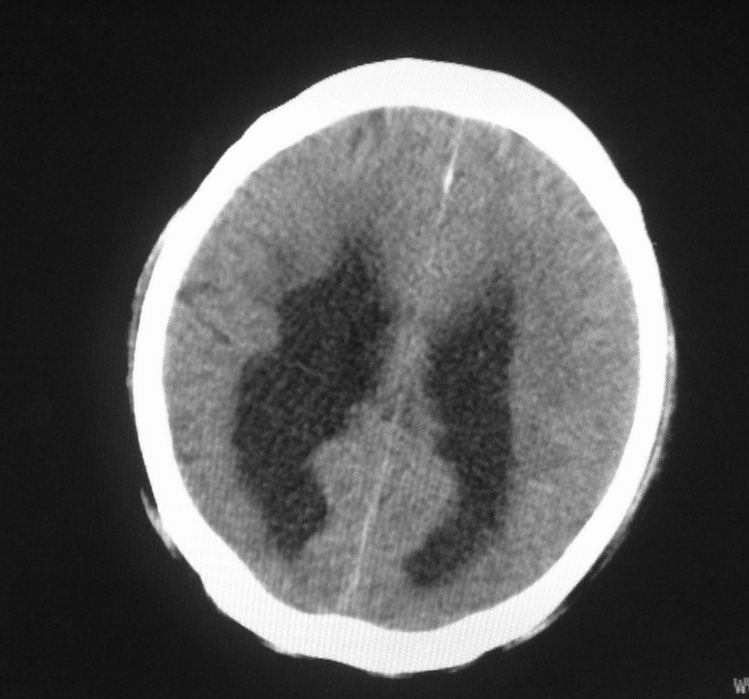

标题: CT24862:男,61岁,发热,有脑出血病史。 [打印本页]

男,61岁,发热,有脑出血病史。

右侧基底节,放射冠软化灶,胼胝体发育不良 脑积水原因待查。

脑积水【脑室血块阻塞?】

脑积水!四脑室显示不清,导水管梗阻?建议mri!

右侧基底节及放射冠软化灶,脑积水,四脑室显示不清,导水管梗阻?建议mri!

梗阻性脑积水,出血后粘连所致

1)右侧基底节区、右侧放射冠及右侧丘脑软化灶。2)脑积水。